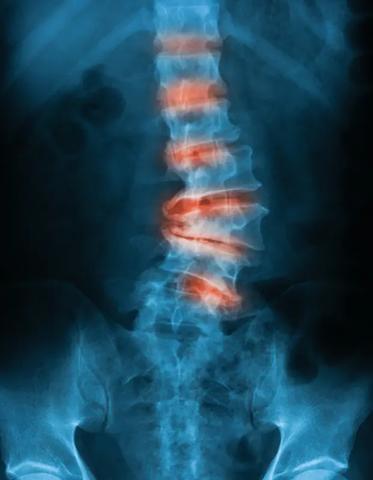

Was ist Spondylose? Ursachen, Symptome und Therapie

Spondylose, auch bekannt als Wirbelgelenksarthrose, ist eine degenerative Erkrankung der Wirbelsäule. Sie tritt häufig im Laufe des Lebens auf und führt zu einem Verschleiß der Facettengelenke, die für die Beweglichkeit der Wirbelsäule verantwortlich sind. Dieser Verschleiß kann zu schmerzhaften Bewegungseinschränkungen führen.

Um eine Spondylose zu erkennen, ist es wichtig, auf mögliche Symptome wie Rückenschmerzen und Bewegungseinschränkungen zu achten. Bei Verdacht auf Spondylose sollte eine Untersuchung durchgeführt werden, um die Diagnose zu bestätigen. Dies kann beispielsweise durch Röntgenaufnahmen oder eine MRT-Untersuchung erfolgen.